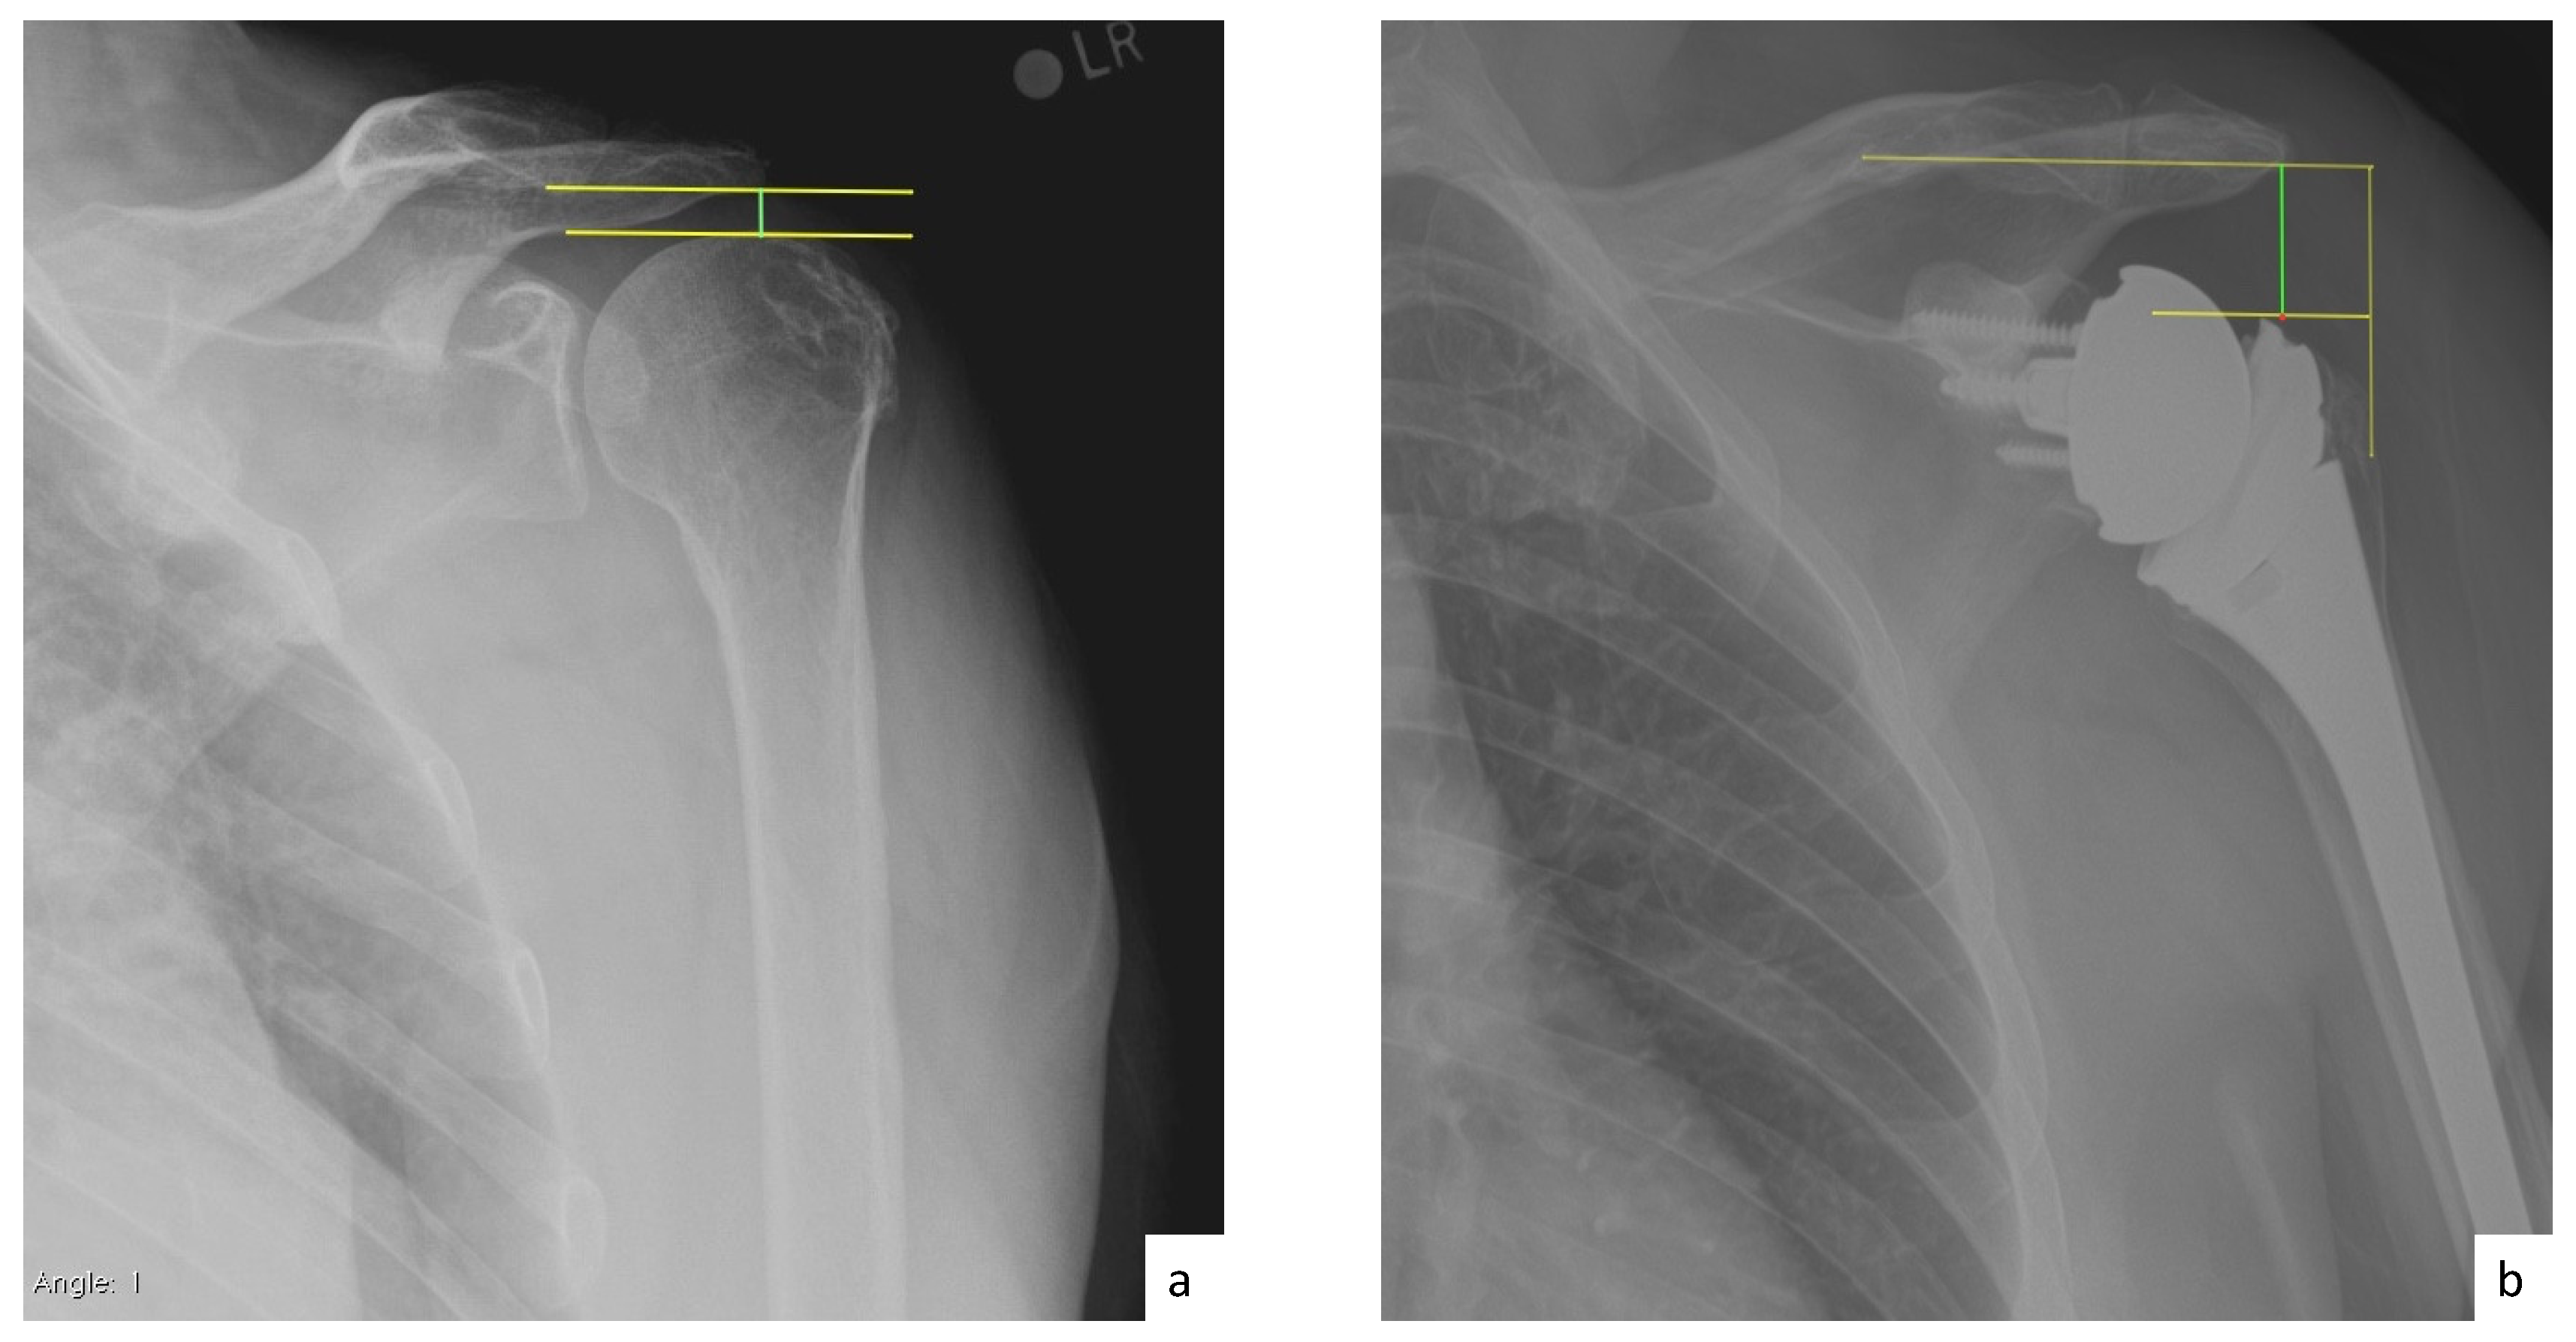

AHD was measured by calculating the perpendicular distance between the most lateral portion of the undersurface of the acromion and a line parallel to the superior border of the greater tuberosity [21] (Figure 1). LHO was measured by determining the distance from the AHD line to the most lateral projection of the greater tuberosity [21] (Figure 2). LSA was measured by drawing a line from the superior glenoid tubercle to the most lateral border of the acromion and a second line from the most lateral border of the acromion to the most lateral border of the greater tuberosity. The angle between these two lines formed the LSA [20] (Figure 3a). DSA was measured by drawing a line between the most lateral border of the acromion and the superior glenoid tubercle and drawing a second line to connect the superior glenoid tubercle with the most superior border of the greater tuberosity. The angle between these two lines formed the DSA [20] (Figure 3b). Glenoid and baseplate were determined as the angle between the floor of the supraspinatus fossa and the glenoid fossa [25] (Figure 4). COR was measured by determining the best fit circle flush to the articular surface, identifying the center of the circle in the humeral head, and then measuring the distance of the perpendicular line between the center of the humeral head and the midpoint of the line connecting the superior and inferior glenoid tubercles [24] (Figure 5b). CSA was measured by a line from the superior pole to the inferior pole of the glenoid and a line from the inferior pole to the lateral edge of the acromion [26] (Figure 5a). In addition, scapular notching was graded according to the Nerot–Sirveaux classification and severity of preoperative cuff tear arthropathy was evaluated according to the Hamada classification [27,28].

Figure 1.

(a) Preoperative acromiohumeral distance (AHD; green line); (b) postoperative acromiohumeral distance (AHD; green line).